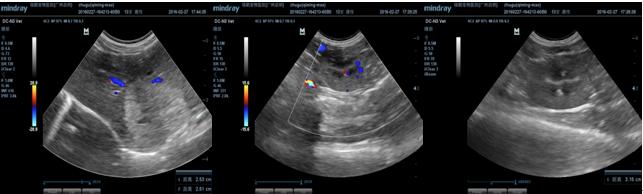

3.2.5 B超检查

超声提示:

1 乳腺肿瘤

2 腹股沟淋巴结炎或腹股沟淋巴结肿瘤

3 肝脏左叶实质结节,疑似肝脏肿瘤。